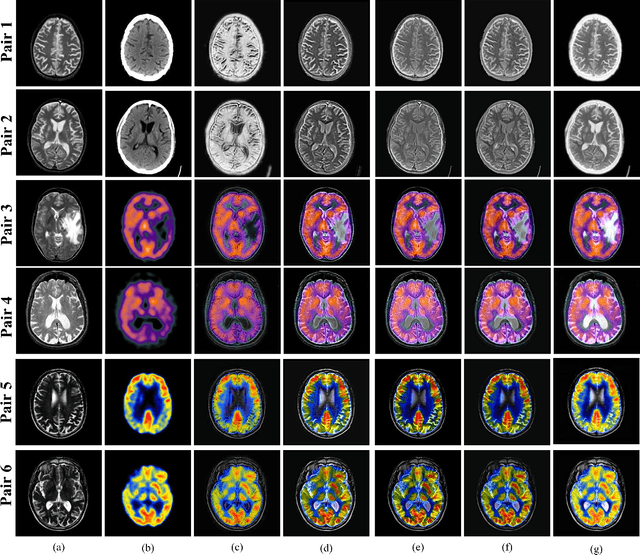

Abstract:Medical image fusion combines the complementary information of multimodal medical images to assist medical professionals in the clinical diagnosis of patients' disorders and provide guidance during preoperative and intra-operative procedures. Deep learning (DL) models have achieved end-to-end image fusion with highly robust and accurate fusion performance. However, most DL-based fusion models perform down-sampling on the input images to minimize the number of learnable parameters and computations. During this process, salient features of the source images become irretrievable leading to the loss of crucial diagnostic edge details and contrast of various brain tissues. In this paper, we propose a new multimodal medical image fusion model is proposed that is based on integrated Laplacian-Gaussian concatenation with attention pooling (LGCA). We prove that our model preserves effectively complementary information and important tissue structures.

Abstract:Medical image fusion integrates the complementary diagnostic information of the source image modalities for improved visualization and analysis of underlying anomalies. Recently, deep learning-based models have excelled the conventional fusion methods by executing feature extraction, feature selection, and feature fusion tasks, simultaneously. However, most of the existing convolutional neural network (CNN) architectures use conventional pooling or strided convolutional strategies to downsample the feature maps. It causes the blurring or loss of important diagnostic information and edge details available in the source images and dilutes the efficacy of the feature extraction process. Therefore, this paper presents an end-to-end unsupervised fusion model for multimodal medical images based on an edge-preserving dense autoencoder network. In the proposed model, feature extraction is improved by using wavelet decomposition-based attention pooling of feature maps. This helps in preserving the fine edge detail information present in both the source images and enhances the visual perception of fused images. Further, the proposed model is trained on a variety of medical image pairs which helps in capturing the intensity distributions of the source images and preserves the diagnostic information effectively. Substantial experiments are conducted which demonstrate that the proposed method provides improved visual and quantitative results as compared to the other state-of-the-art fusion methods.